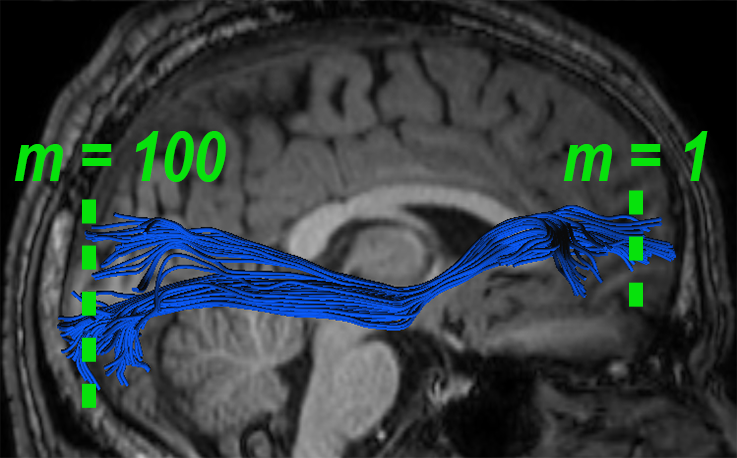

Experiments also showed significant FFDD longitudinal changes between mid-season and post-season scans in some football players. Fig. 7 presents mid- and post-season MD-FFDD profiles comparison of the left IFOF of one of the players, showing increased irregularities over time at the occipital part of the tract. Fig. 8 presents a similar MD-FFDD longitudinal analysis of the FMT of a different player, showing increased irregularities at the central part of the tract.

| Mid vs. Post | Mid-season | Post-season | ||

|---|---|---|---|---|

![]() |

|

STDs |